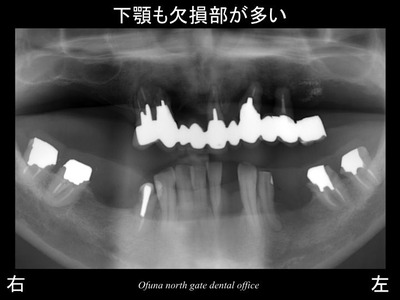

下顎も欠損が多くあります。

上顎の歯は残せる状態ではありませんでした。

全て抜歯となります。